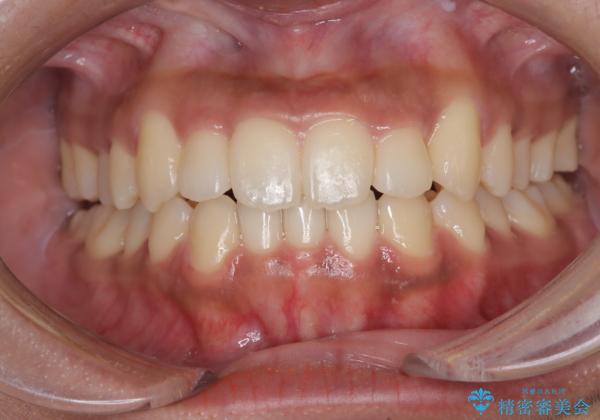

【インビザライン】笑ったときに目立つ八重歯をなおしたい

下の前歯が一本足りない患者様でしたので、シミュレーションを作り、事前に患者様と治療ゴールのイメージをしっかり共有したうえでインビザラインを用いて治療を行っています。

奥歯を後ろのほうに動かすことで、前歯も少し下がることができ、矯正後の口元も満足していただきました。

下顎の前歯が一本ない場合は上下の正中は合いません。